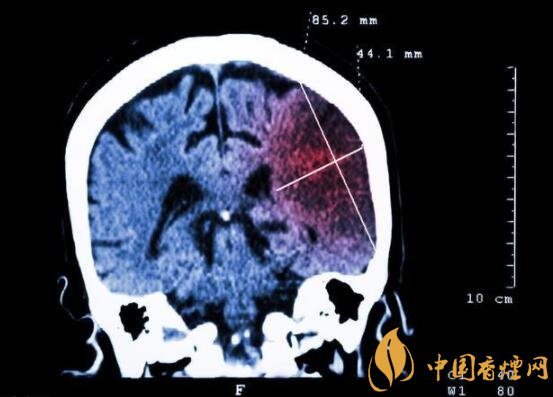

一般而言,急性脑梗塞与长期吸烟有非常密切的联系。有长期烟龄遇到肢体活动不顺,做头颅核磁共振检查往往查出一侧大脑中动脉闭塞的可能性很高。由此可见,吸烟确实与中风存在一定联系。